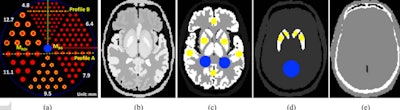

At the heart of the new design is a variable-aperture ring geometry (small detector modules moving radially in and out) that would allow the researchers to image subjects within the field of view in high resolution in all possible angular positions. Their system comprises eight large-area CZT detectors, as opposed to conventional SPECT systems with two-head Anger detectors.

To evaluate the imaging performance of their proposed SPECT-CZT system, they used digital phantoms and realistic digital brain phantoms for conventional SPECT systems with comparable pixel sizes and radii of rotation. The proposed scanner offered image acquisition results up to approximately three times faster in acquisition time over conventional scan time at the same acquisition time per step.